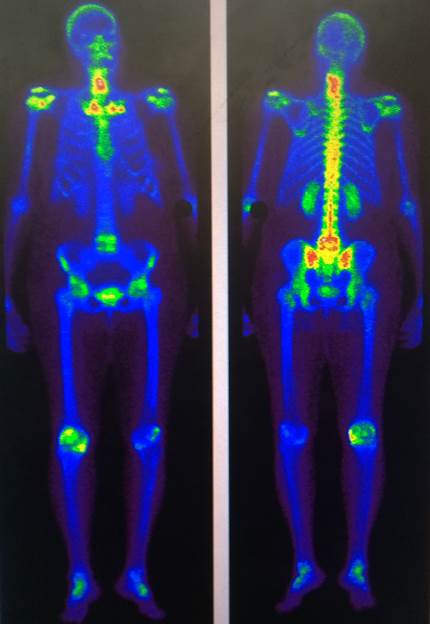

Gammagrafía ósea: Focos de captación en vértebras cervicales inferiores con comportamiento inespecífico, no pudiéndose descartar origen metastásico. (Figura 2).